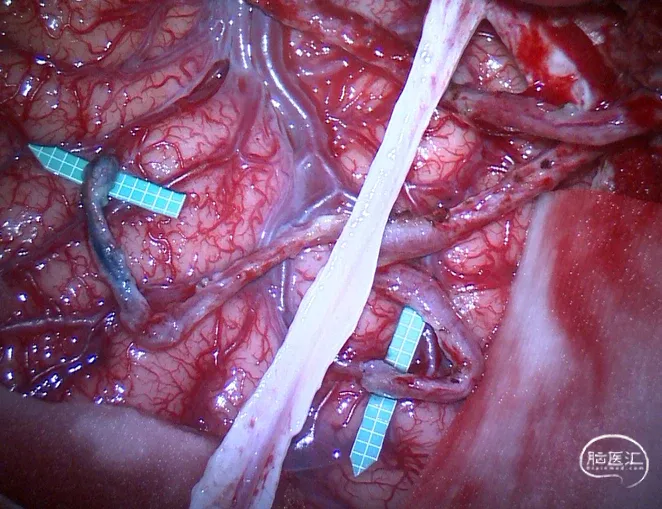

图3 STA-ACA,STA-MCA三吻合术中所见:上图,右大脑前动脉位于额上回表面,直径1 mm;大脑前动脉与额叶脑组织之间植入带1 mm白色网格的绿色乳胶血管垫片;

中图,行右颞浅动脉额支与大脑前动脉端侧吻合,白色大脑镰位于额叶中线侧;

下图,行右颞浅动脉顶支的两支与额下回、颞上回表面大脑中动脉端侧吻合,术区中央浅部为脑膜中动脉及其附着的硬脑膜。【18】